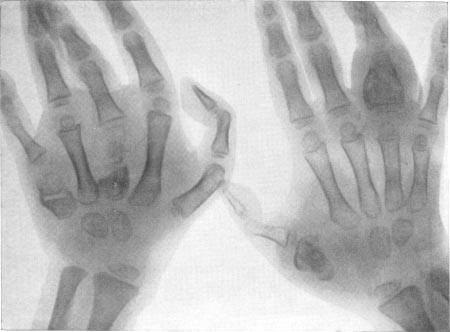

- Туберкулез лучезапястных суставов;

Спондилит вызывает искривления спины, приводит к росту горба и параличу конечностей (в тяжёлых случаях). Последствия коксита – деформация и патологический вывих тазобедренного сустава; туберкулеза голеностопа – неподвижность сустава в результате сращения его поверхностей. Туберкулез запястий встречается нечасто, для него характерно поражение обеих рук и сочетание с гонитом или оленитом. Туберкулез трубчатый костей (поражающий фаланги кистей и пястные кости) – очень редкий вид, наблюдается преимущественно у детей до трех лет.